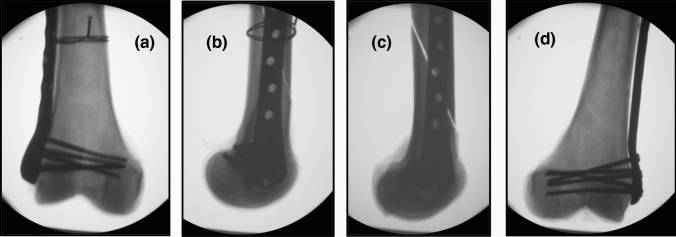

Fig. 3.

Typical postoperative X-ray pictures showing a pair of samples with an NCB-DF plate osteosynthesis and an additionally attached double-looped wire cerclage in the right femur (a and b) (the same femur is shown in Fig. 2). The left femur only received fixation with an NCB-DF plate (c and d)

In both groups, the same three different failure modes occurred. Deformation of the construct due to irreversible bowing of the plate osteosynthesis occurred twice in the conventional group and once in the group with an additional wired cerclage (Fig. 6a). Multifragmentary femoral shaft fracture with cutting out of the shaft screws occurred once in both groups (Fig. 6b). Shearing of the condylar region with cutting out of the condylar screws was the most frequent reason for failure in both groups, with six incidences in the cerclage group and five in the conventional group (Fig. 6c). In all specimens with wire cerclage, the dorsal buttress broke under the cerclage, while just one out of eight specimens in the conventional group experienced this type of breakage. Figure 6d shows the corresponding X-ray pictures to the failure mode that most frequently occurred.

Fig. 6.

Photographs showing the different types of construct failure. Reasons for failure included irreversible deformation of the osteosynthesis plate (a) and multifragmentary fracture of the femoral shaft (b). Most common in both groups was failure due to cutting out of the screws (c 1–4) with shearing away of the condylar region. In most specimens with wire cerclage, the dorsal buttress broke under the cerclage at this failure mode. (d 1 and 2) illustrate the corresponding X-ray pictures to the specimen shown in (c 2 and 3)